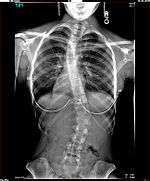

Paul Randall Harrington (September 27, 1911 – November 29, 1980) was an American orthopaedic surgeon. He is best known as the designer of the Harrington Rod, the first device for the straightening and immobilization of the spine inside the body. It entered common use in the early 1960s and remained the gold standard for scoliosis surgery until the late 1990s.[1] During this period over one million people benefited from Harrington's procedure.

The Harrington Rod

The Harrington Rod, or Harrington implant, is a device for the straightening of the spine inside the body, designed by Paul Harrington. The device consists of a stainless steel rod, attached to the spine at the top and bottom of the curve with hooks. Attached ratchets are then tightened to distract or straighten the spine. Following surgery to insert the rod, the patient wears a postoperative plaster cast or brace for a few months, until vertebral fusion has occurred, after which the cast or brace is removed.[5]

The major drawback of the Harrington Rod is that it straightens out the normal front to back curvature of the segment of the spine that is fused, which in many patients results in a flat back deformity, also known as "flatback syndrome". Advances in surgical techniques and technology in the late 1990s were eventually able, in most cases, to correct scoliosis without causing flatback syndrome, leading to the gradual phasing out of the Harrington Rod.[6]